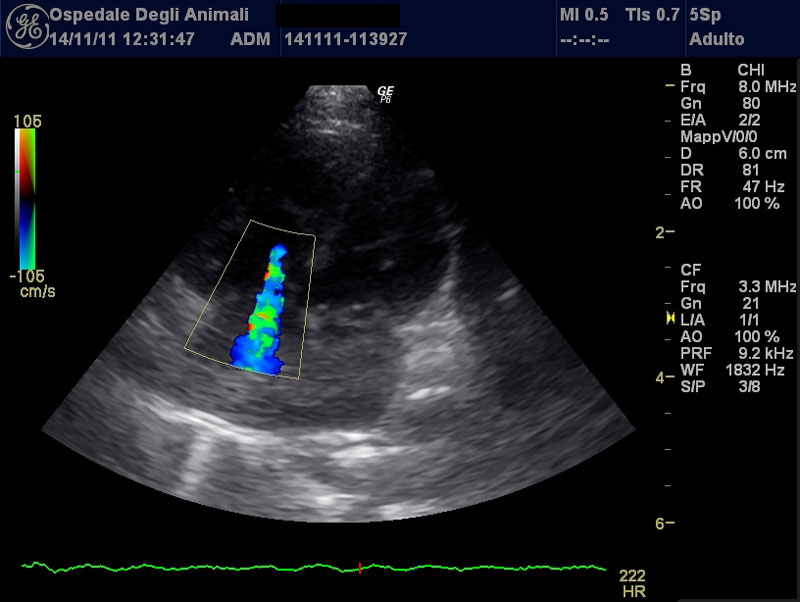

L'ecografia e l'ecocardiografia sono branche della diagnostica per immagini che utilizzano gli ultrasuoni per ottenere indagare organi ed apparati, con un ruolo fondamentale nell'iter diagnostico di molte patologie.

L'Ospedale degli Animali dispone di un ecografo di ultima generazione, fornito di modulo doppler ed eco-doppler e di vari tipi di sonde, che permette un esame completo ed accurato su diverse tipologie di pazienti e di strutture anatomiche.

Si eseguono ecografie addominali, ecografie toraciche, ecografie al collo, all'occhio e muscolo-tendinee, ecocardiografie, aghiaspirati e biopsie ecoguidate (procedure eseguite alla presenza di un anestesista).

Si eseguono inoltre procedure interventistiche d'urgenza ecoguidate (pericardiocentesi, toracocentesi)